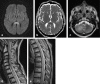

Background and purpose: The splenium of the corpus callosum is the most posterior part of the corpus callosum. Its embryological development, anatomy, vascularization, function, imaging of pathology, possible pathophysiological mechanisms by which pathology may develop and the clinical consequences are discussed.

Methods: A literature-based description is provided on development, anatomy and function. MR and CT images are used to demonstrate pathology. The majority of pathology, known to affect the splenium, and the clinical effects are described in three subsections: (A) limited to the splenium, with elaboration on pathophysiology of reversible splenial lesions, (B) pathology in the cerebral white matter extending into or deriving from the splenium, with special emphasis on tumors, and (C) splenial involvement in generalized conditions affecting the entire brain, with a hypothesis for pathophysiological mechanisms for the different diseases.

Results: The development of the splenium is preceded by the formation of the hippocampal commissure. It is bordered by the falx and the tentorium and is perfused by the anterior and posterior circulation. It contains different caliber axonal fibers and the most compact area of callosal glial cells. These findings may explain the affinity of specific forms of pathology for this region. The fibers interconnect the temporal and occipital regions of both hemispheres reciprocally and are important in language, visuospatial information transfer and behavior. Acquired pathology may lead to changes in consciousness.